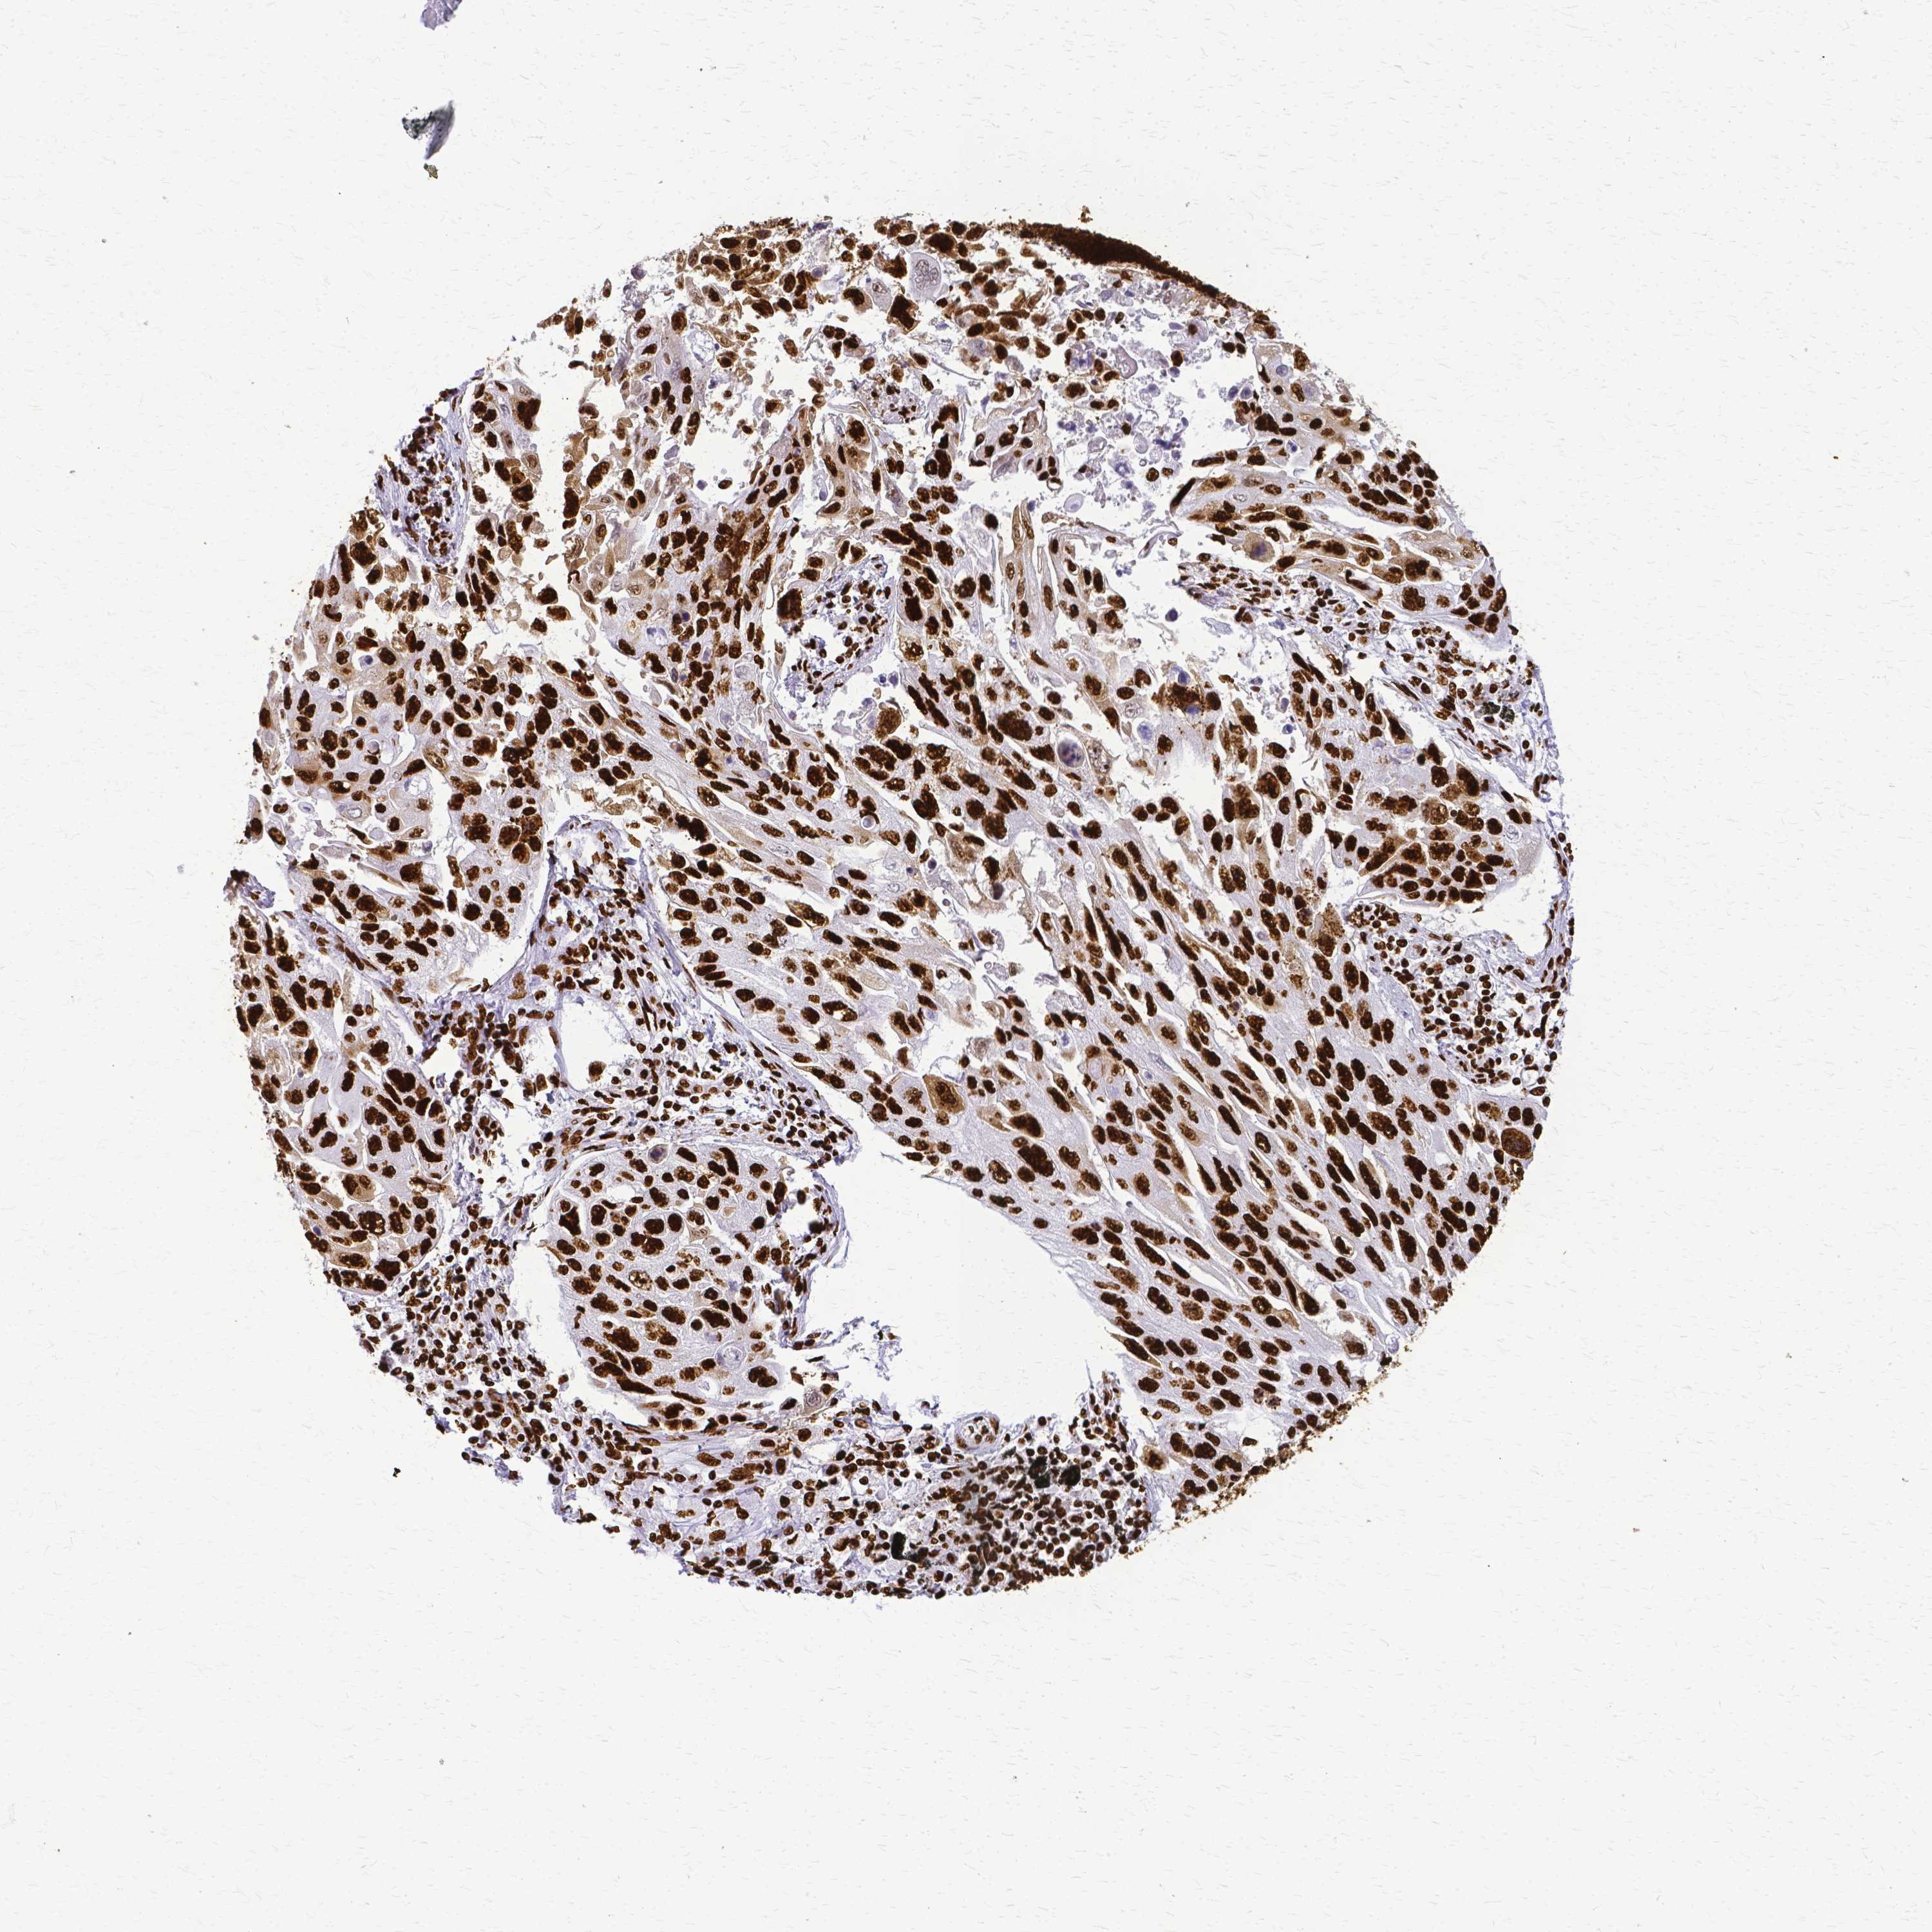

CANCER LUNG CANCER Show tissue menu

LUAD TCGA LUAD VALIDATION LUSC TCGA LUSC VALIDATION PROTEIN LUAD CPTAC PROTEIN LUSC CPTAC PROTEIN EXPRESSION